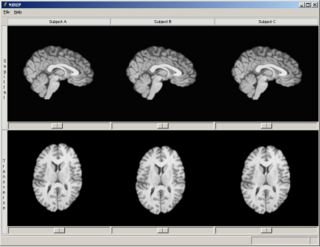

We have started the Non-rigid Image Registration Evaluation Project (NIREP) to develop software tools and provide shared image validation databases for rigorous testing of non-rigid image registration algorithms. NIREP will extend the scope of prior validation projects by developing evaluation criteria and metrics using large image populations, using richly annotated image databases, using computer simulated data, and increasing the number and types of evaluation criteria.

The goal of this project is to establish, maintain, and endorse a standardized set of relevant benchmarks and metrics for performance evaluation of nonrigid image registration algorithms. Furthermore, these standards will be incorporated into an exportable computer program to automatically evaluate the registration accuracy of nonrigid image registration algorithms.

- Display manager is responsible for displaying images, landmarks, contours, surfaces, and associated semantic information. It also displays metric information in various formats. The display is described in an XML (MRML) description.